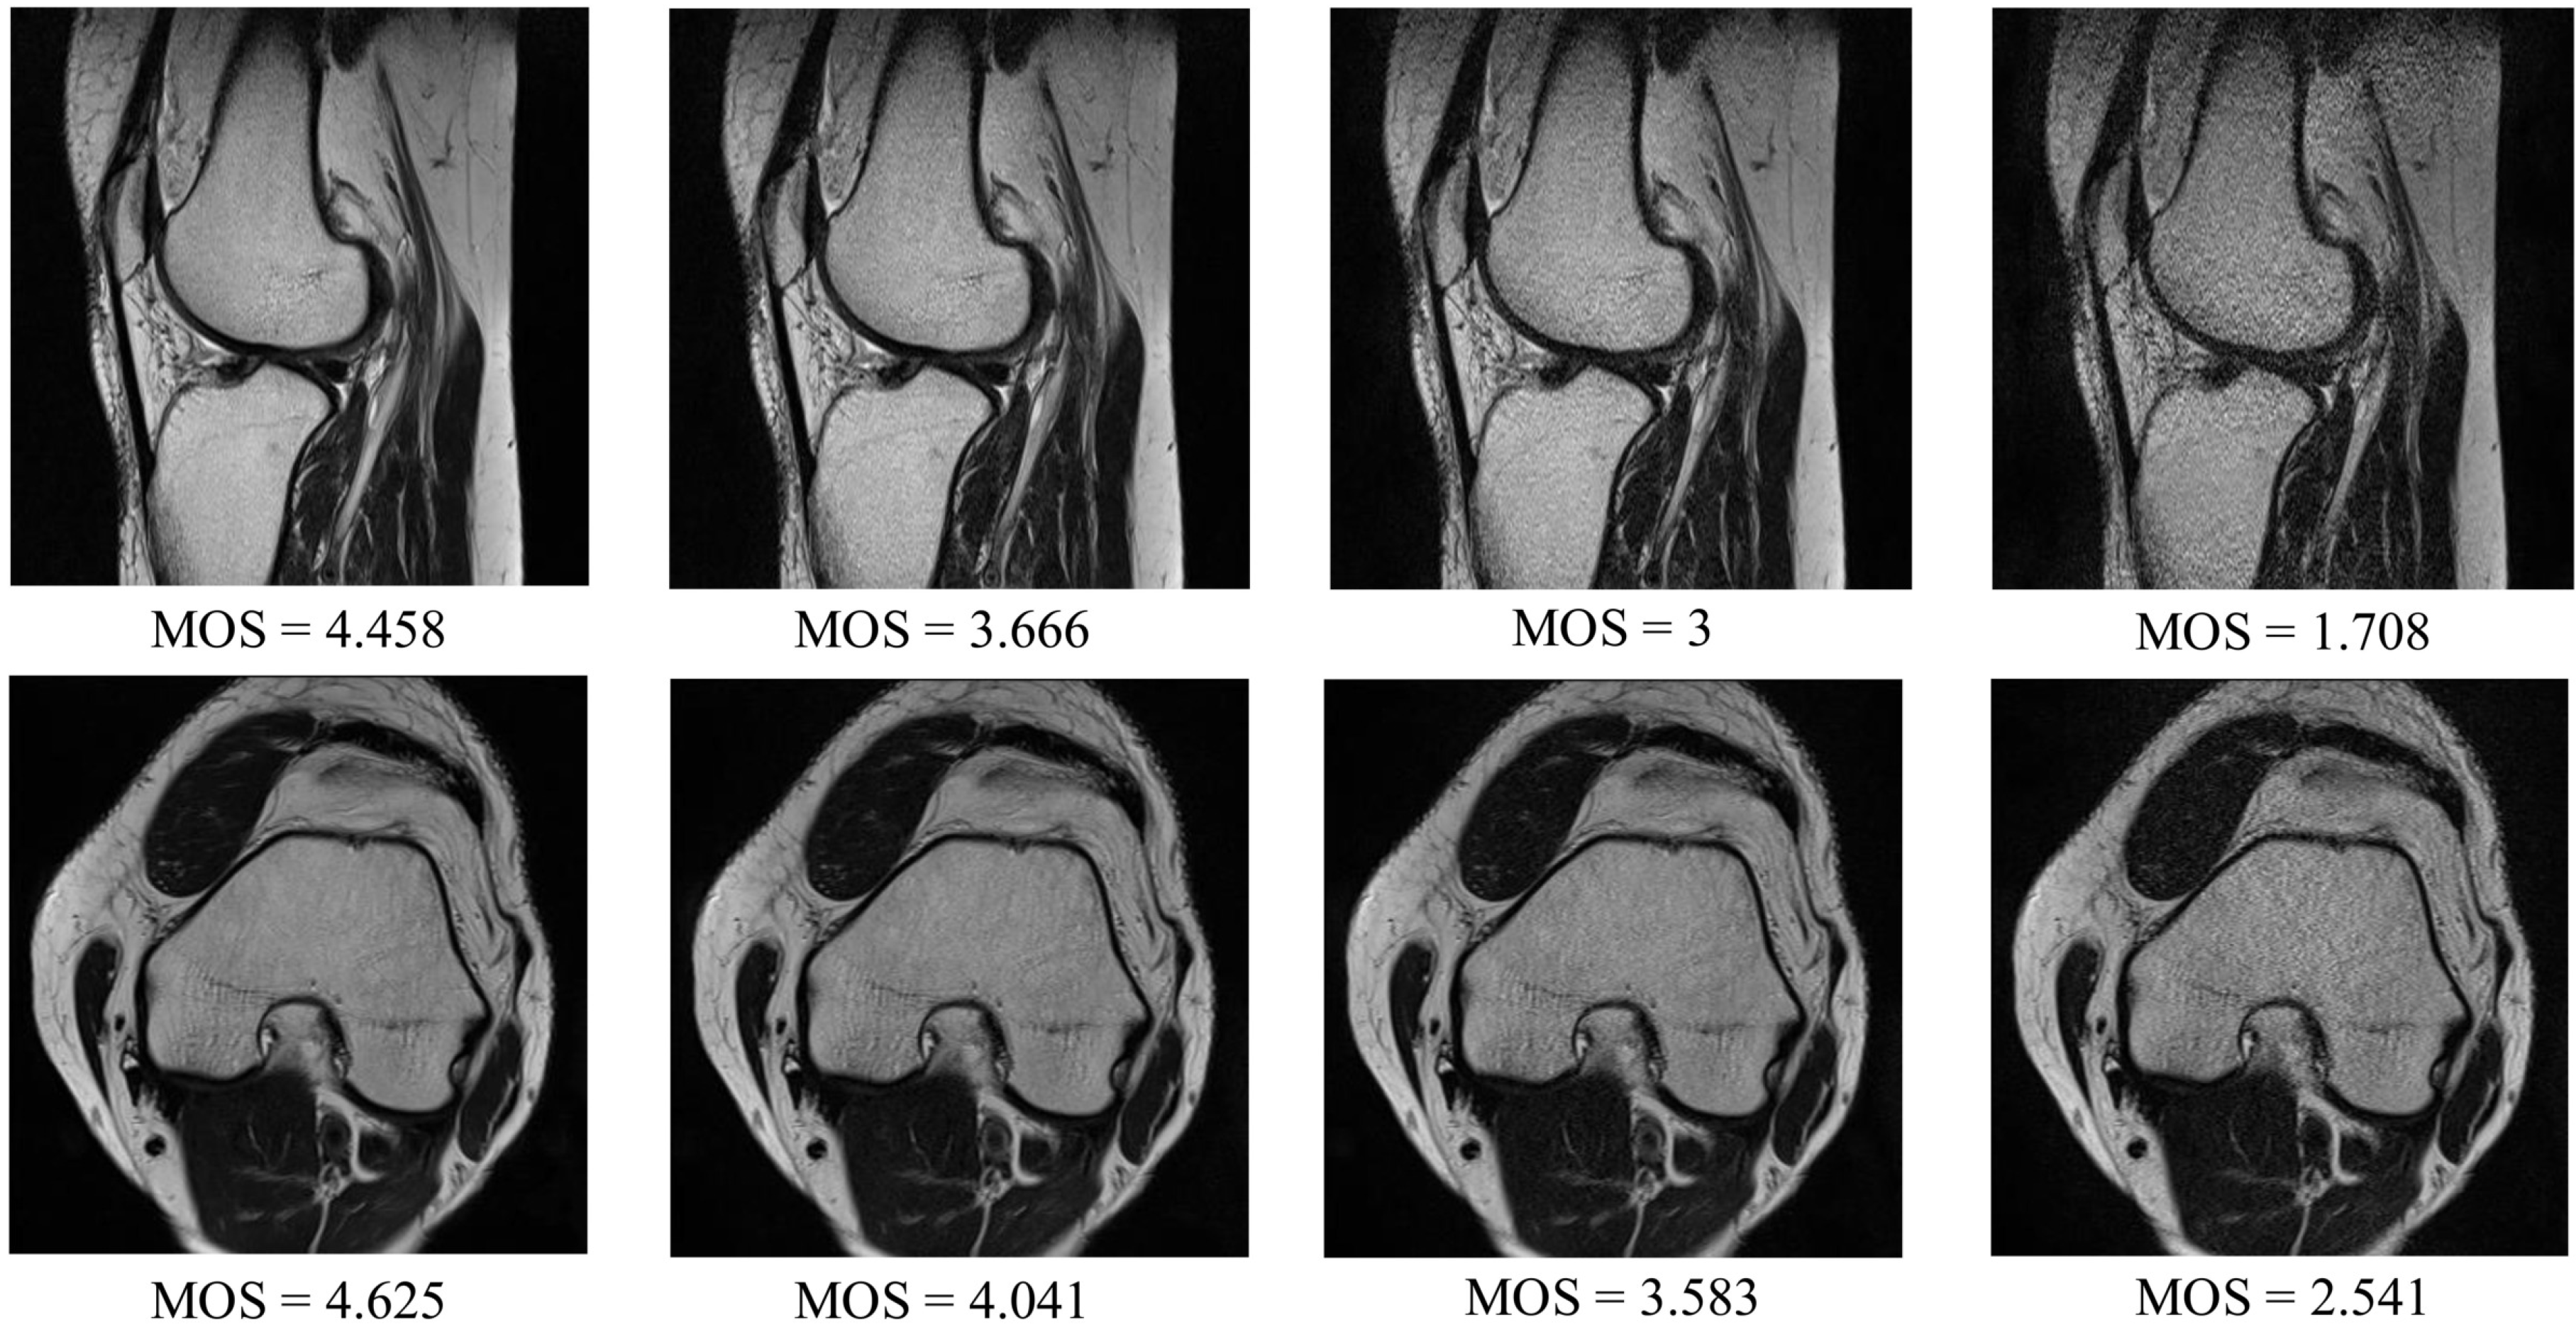

4.1. Experimental Data